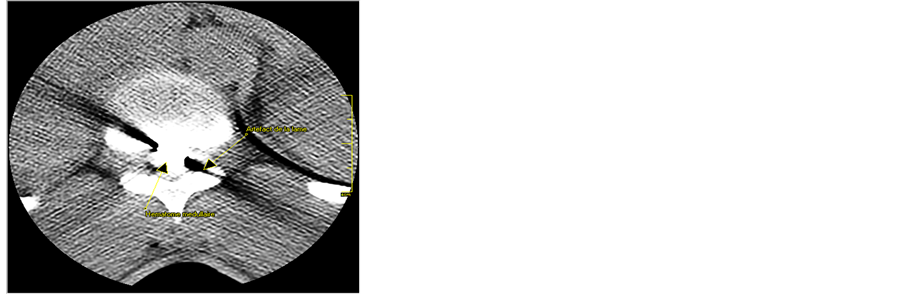

In the emergency Ward, sterile dressing of the wound was done, an intravenous line was inserted, blood samples were collected, and antibiotics were started along with high dose methylprednisolone (Houde laboratories, Paris, France) protocol (30 mg/kg IV infusion in one hour and then 5.4 mg/kg given over 23 hours). After that, a computed tomography (CT, Toshiba, Tokyo, Japan) scan of thoracolumbar spine was done. It revealed: vertebral and spinal cord injury with an incarcerated 8 cm broken knife blade, complete spinal cord transection at T11 - T12 level, and hyper intense hematoma along the wound tract (Figure 1). The patient was operated as an emergency under general anesthesia with endotracheal intubation. A midline posterior approach extending between T9 and T12 levels was performed. Opening of the superficial dorsal aponeurosis immediately revealed the incarcerated knife blade. Para spinal muscles were severed subperiostly, spinous processes removed and T11 - T12 laminectomy was done. It was noticed that the knife had broken the T12 spinous process, torn the spinal dura, transected the spinal cord and got stuck into the inferior part of T11 vertebral body. The incarcerated broken knife blade was gently pulled out with a rongeur. This revealed the spinal cord transection with a compressive hematoma at the injury site. The hematoma was removed with smooth suction and spinal cord wound washed with warm normal saline. Dura opening was sutured with 3/0 nylon sutures and the wound closed in layers (Figure 2). The immediate postoperative period was marked by a rapid recovery of motility and sensation so that at two weeks after surgery, muscle strength was at least 3 in all muscle groups ensuring motility of lower limbs till the legs. Nevertheless, motility of the feet remained null (level L5 and below). The patient was discharged from hospital on day 14 after surgery for a rehabilitation center. Thirty two months after surgery, patient’s neurological status was unchanged although he mentioned a slight improvement in sphincter disturbances.

Spinal cord stab injuries (SCSI) are most often located in the thoracic spine as in this case, followed by cervical and lumbar areas [2] [3] [5] [8] [9] . The usual clinical presentation of SCSI is incomplete paraplegia manifesting most often as Brown-Séquard syndrome [1] [4] [8] . In the case reported here, paraplegia was complete. The majority of patients with SCSI have sphincter disturbances most often urinary. Complete spinal cord transection as in this case is rarer. Our observation has revealed that part of the neurologic symptoms can be provoked by hematoma within or around the spinal cord or post traumatic edema. Rapid recovery of muscle strength in most muscle groups in this case was probably due to release of spinal cord compression caused by intra spinal cord hematoma (Figure 2). The patient came with complete paraplegia at the thoracic level 10, but two weeks later, the persistent neurological deficits concerned only levels from L5 and below. This neurological status persisted until the last follow up visit (32 months). Other mechanisms which can explain acute neurological deficits in patients with SCI are: transection of nervous elements, spinal cord infarct due to blood vessels’ injury or compression, and more rarely spinal cord epidural hematoma [4] .

Concerning prognosis, SCSI have a heavy impact on the victims, families and the entire society in terms of autonomy loss, working time loss, functional disability, the financial and human costs. Nevertheless, SCSI has a better prognosis (motor recovery and sphincter control) than other traumatic SCI, especially injuries due to guns. This is explained by the fact that in SCSI, incomplete injuries are much more frequent [1] [3] [4] [7] - [9] . More than half of incomplete paraplegics recover autonomy for walking with or without prosthesis and 71% in the series from Waters et al. achieved voluntary control of their bladder voidance [1] . Yeung has pointed out the role of spinous processes which make midline penetration of the knife more difficult [5] . Conversely, motor recovery with walk autonomy is very rare in case of complete neurological deficit as it was in the reported case. The T10 level complete paraplegia in our patient and it rapid regression till L5 level could be explained by release of cord compression due to associated hematoma (Figure 2).